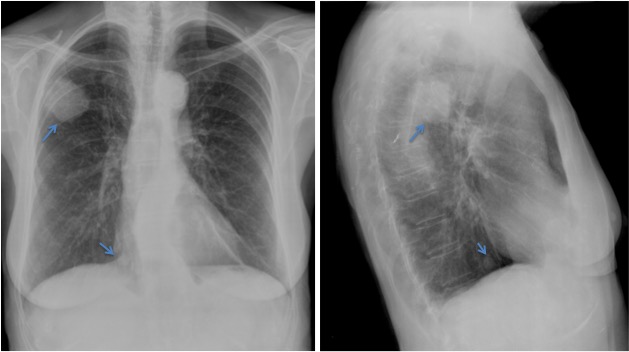

CASO: Febrícula y tos de 4 días de evolución.

Hallazgos:

- En la placa PA se observa una asimetría en los hilios pulmonares, el hilio izquierdo tiene una densidad aumentada.

- Tras examinar la placa lateral se observa un aumento de densidad en la columna que puede ser compatible con una condensación, es el signo de la desnificación vertebral.

SIGNO DE LA DENSIFICACIÓN VERTEBRAL: En la radiografía lateral normal, la densidad de la columna torácica tiende a disminuir desde la parte superior hasta el diafragma; la alteración de ese patrón por la presencia de una densidad superpuesta a la columna, indica la existencia de una consolidación pulmonar. Este signo adquiere especial valor cuando en la proyección posteroanterior la consolidación está oculta en el espacio retrocardíaco o en la base pulmonar.